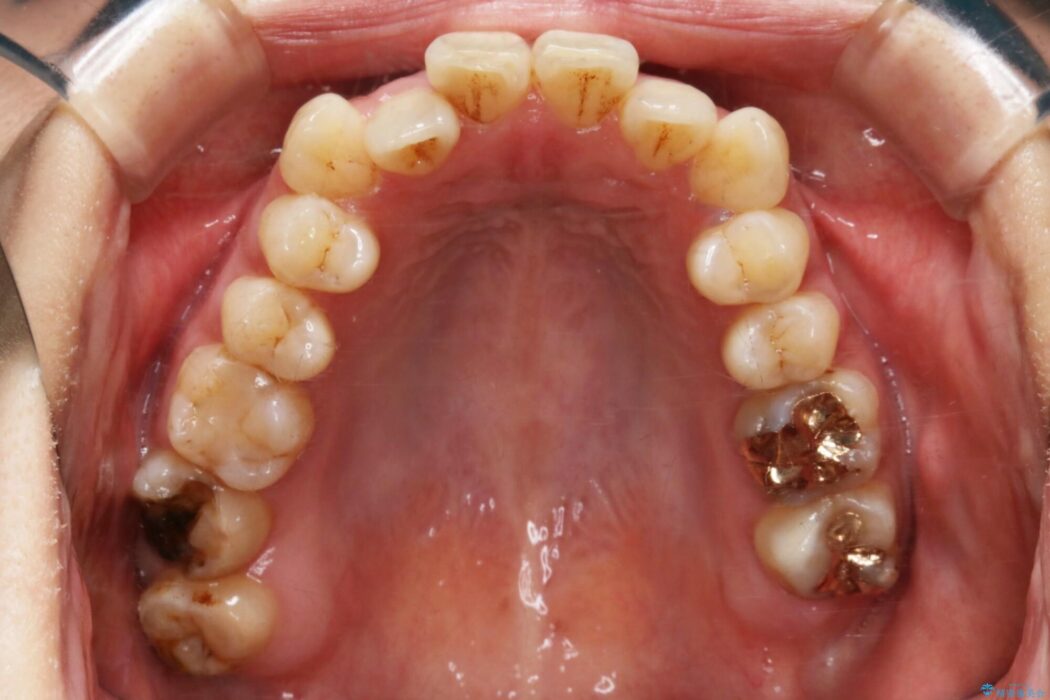

開咬により上下の噛み合わせが悪く、歯列の凸凹も合わせて治療したいとのことで来院されました。

なるべく非抜歯にて治療をするためインビザライン(マウスピース)とマイクロインプラントを併用した治療を行いました。

マウスピースとマイクロインプラントの併用により矯正するための隙間を確保し、治療期間は長くなりますが非抜歯できれいな歯列弓を得ることができます。